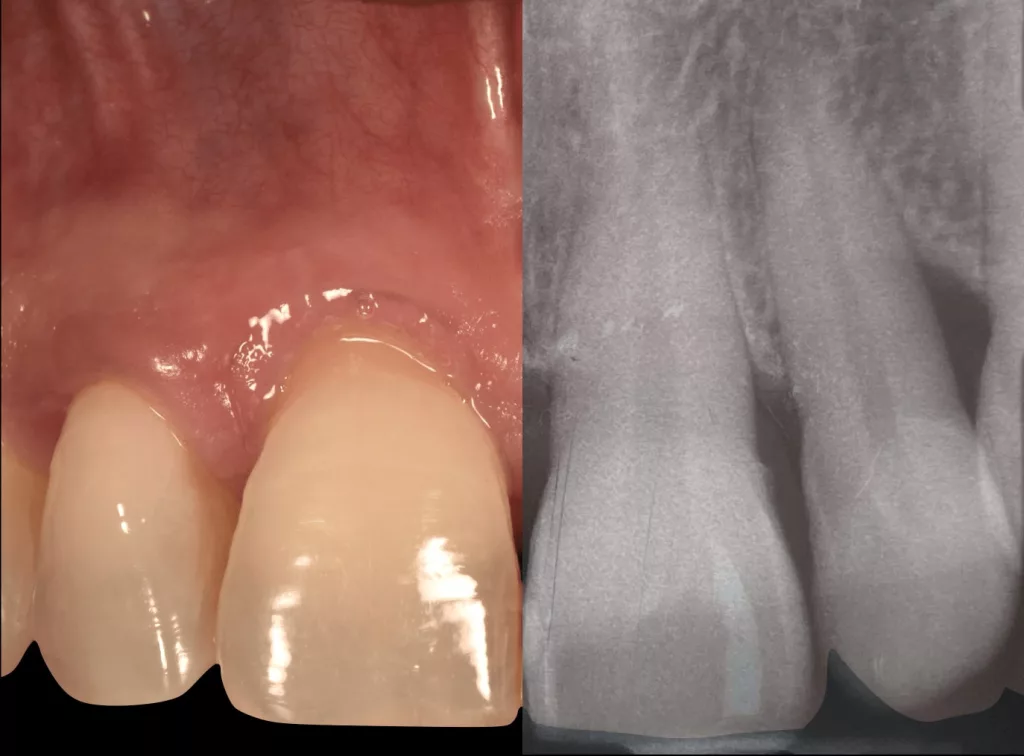

L’un des symptômes de la maladie parodontale est la visibilité des racines des dents par rétractation des gencives, également appelée récession gingivale.

Cette dénudation de la surface dentaire peut également intervenir en cas de frottement mécanique trop intense au niveau de la zone, par exemple avec un brossage traumatique.

Le sondage est réalisé à l’aide d’une sonde parodontale millimétrée. 6 mesures sont réalisées au niveau de chaque dent, 3 au niveau de la face avant et 3 au niveau de la face arrière.

Cet examen permettra de mesurer la profondeur des poches parodontales. La poche est l’espace formé entre la gencive et la surface de la dent par la maladie parodontale.